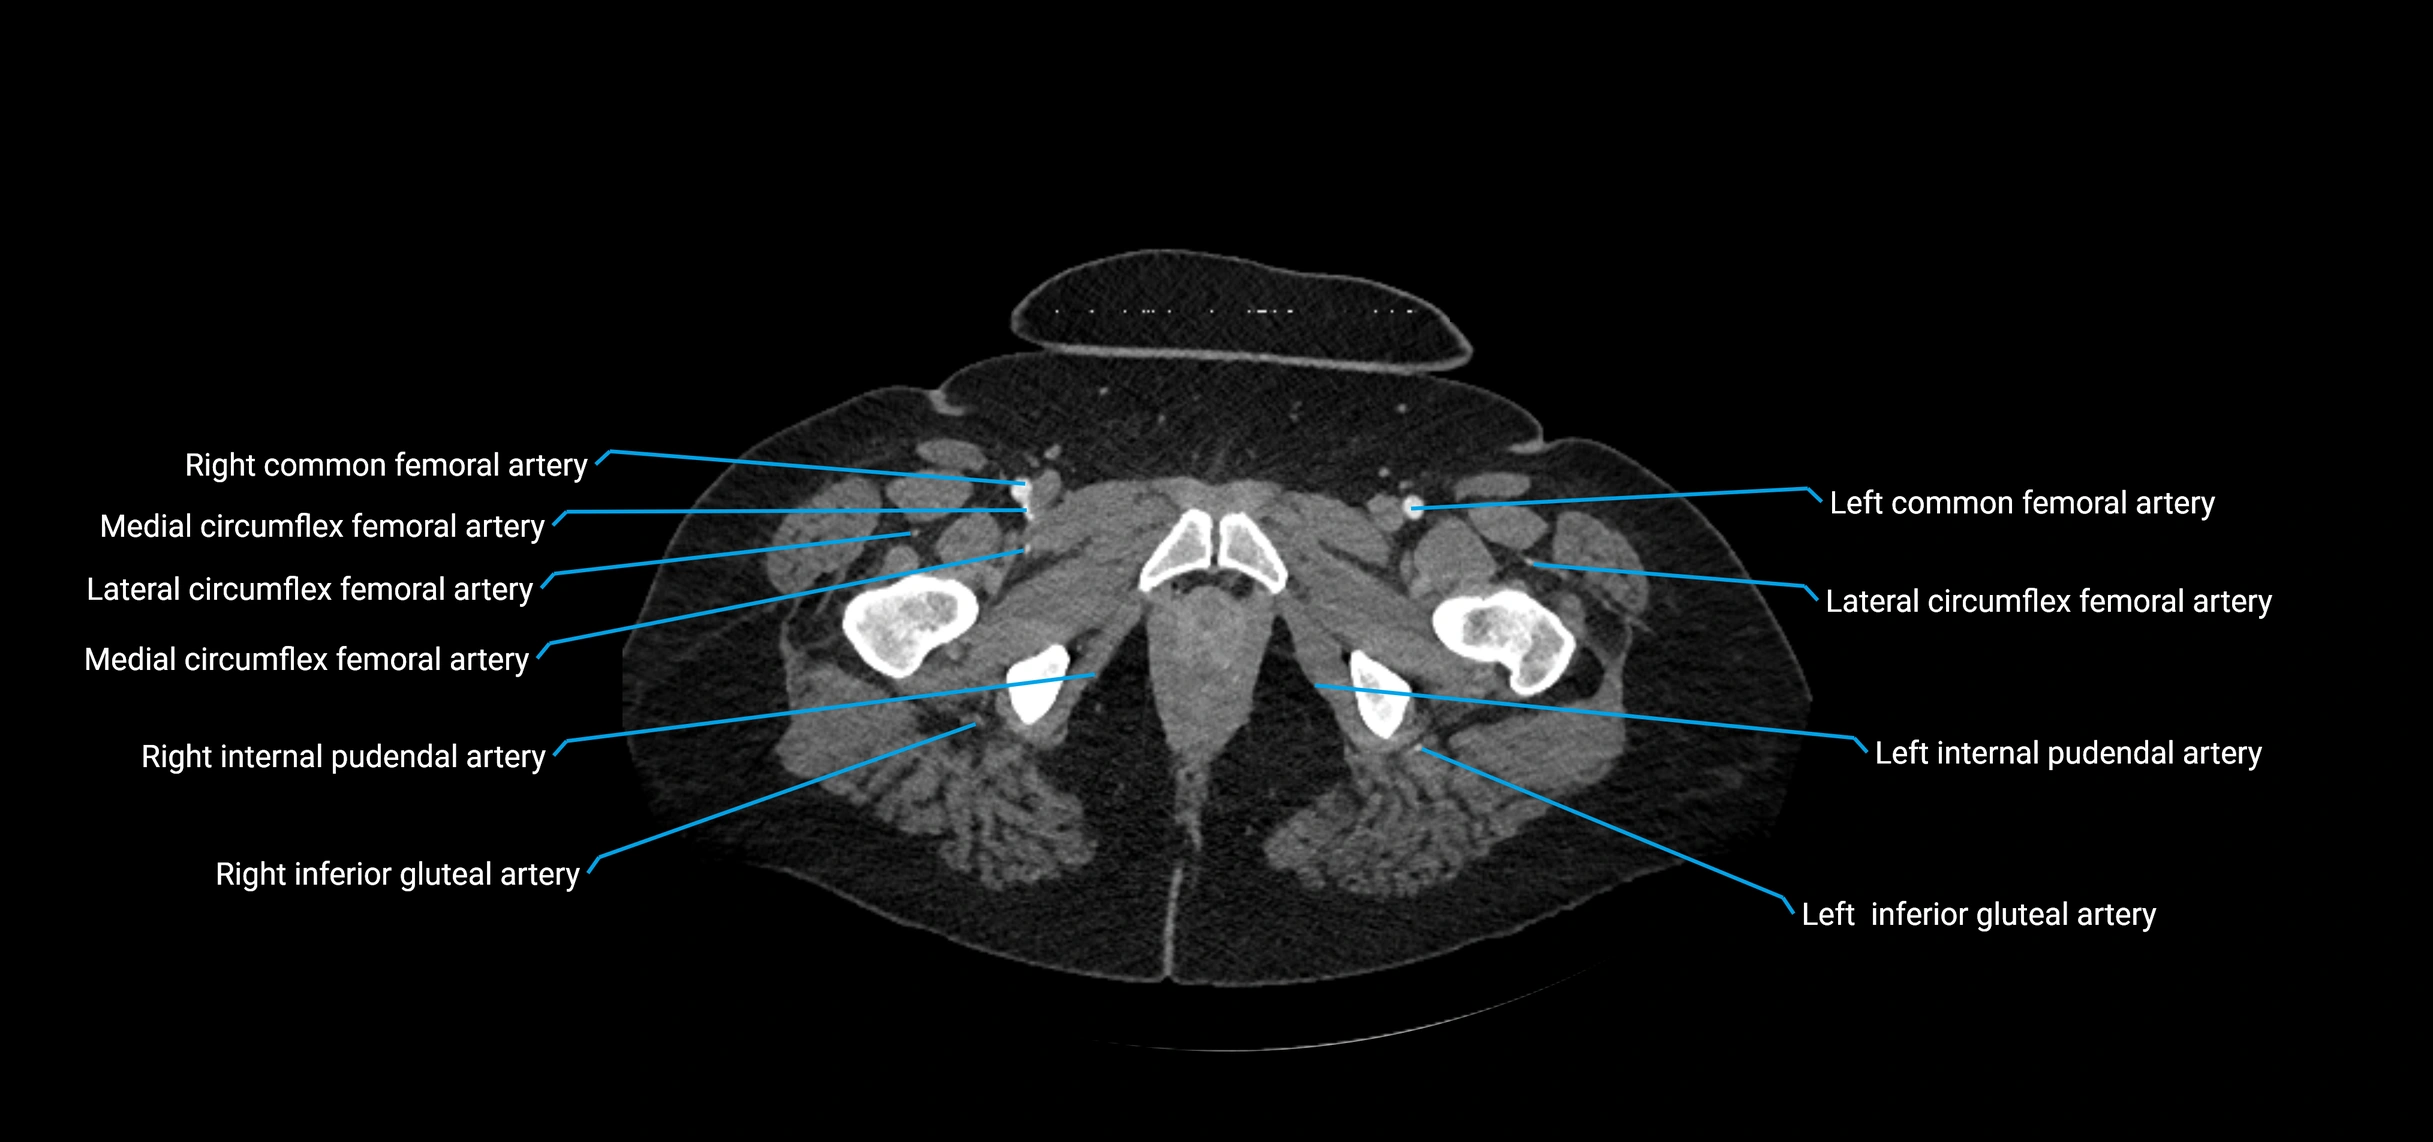

CT Appearance

Non-contrast CT:

• Appears as a tubular soft tissue structure anterior to vertebral bodies

• Calcified atherosclerotic plaques appear as hyperdense foci along the wall

• Useful for screening abdominal aortic aneurysm (AAA) size and mural calcification

Contrast-enhanced CT (CTA):

• Gold standard for abdominal aortic imaging

• Provides excellent detail of lumen, wall, aneurysm, thrombus, and branch vessels

• Multiplanar and 3D reconstructions help in aneurysm measurement, stent graft planning, and dissection evaluation

• Detects acute rupture, traumatic injury, or occlusion with high sensitivity

CT images

image